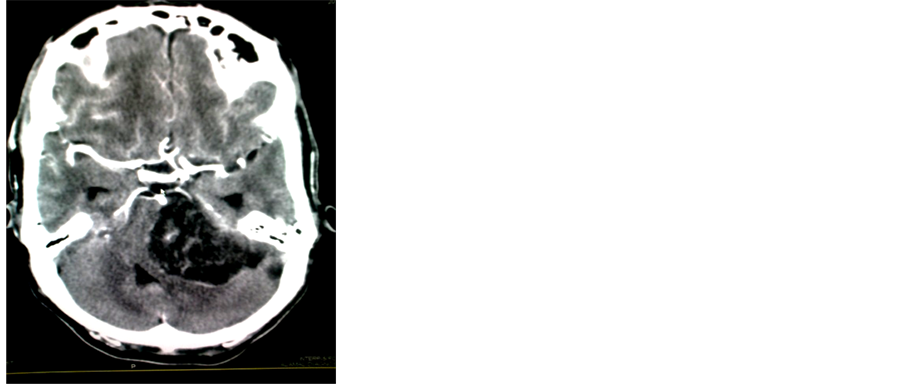

In the diagnosis of 100 cases of brain glioma the CT scan diagnoses (64 patients) (63.4%), and after the biopsy result confirmation the number of the patients decreased to (39 patients) (38.6%) as in image in Figure 1 and Figure 2.

Figure 1. The diagnosis of brain astrocytoma by CT & tissue biopsy.

Figure 2. Axial CT brain images (b) without contrast and (a) with contrast showed a mixed lesion in the left cerebellar hemisphere crossing the midline with contrast enhancement. Astrocytoma.